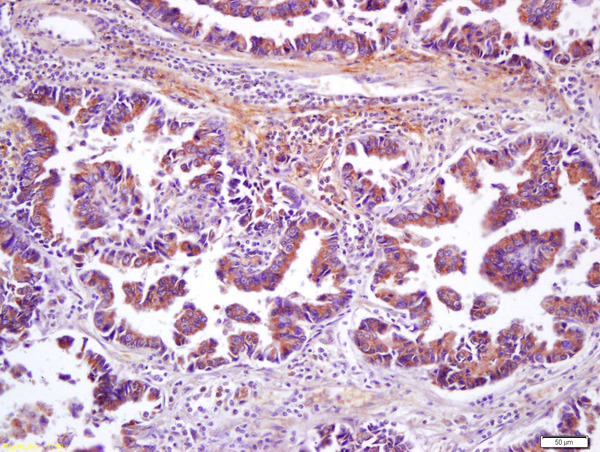

- Main image

- Experimental details

- Formalin-fixed and paraffin embedded human lung carcinoma labeled with Anti-Wnt8b Polyclonal Antibody, Unconjugated (bs-6245R) at 1:200 followed by conjugation to the secondary antibody and DAB staining

- Sample type

- Human

- Other comments

- Lung